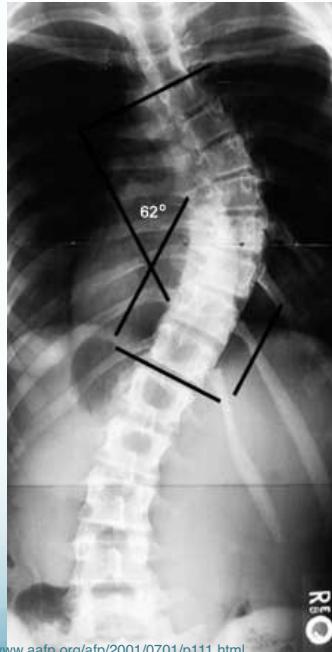

Cobb’s Angle

- Measures the amount of curve

- Angle between perpendicular lines to the uppermost and lowermost vertebral bodies in the curve

Cobb Angle Measurement

- Select most tilted vertebrae above and below curve apex

- Angle between intersecting lines drawn perpendicular to superior vertebra top and inferior vertebra bottom